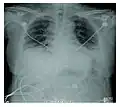

Rapid progression from initial symptoms to respiratory failure is a key feature. An X-ray that shows ARDS is necessary for diagnosis (fluid in the small air sacs (alveoli) in both lungs). In addition, a biopsy of the lung that shows organizing diffuse alveolar damage is required for diagnosis. This type of alveolar damage can be attributed to nonconcentrated and nonlocalized alveoli damage, marked alveolar septal edema with inflammatory cell infiltration, fibroblast proliferation, occasional hyaline membranes, and thickening of the alveolar walls. The septa are lined with atypical, hyperplastic type II pneumocytes, thus leading to the collapse of airspaces. Other diagnostic tests are useful in excluding other similar conditions, but history, X-ray, and biopsy are essential. These other tests may include basic blood work, blood cultures, and bronchoalveolar lavage.

Acute interstitial pneumonia showing a marked reduction in lung capacity